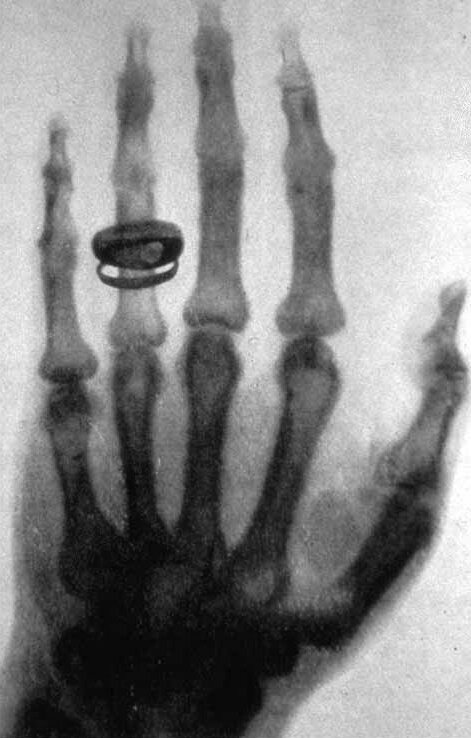

Предыстория ядерной медицины началась в 1895 году, когда Вильгельм Рёнтген открыл Х-лучи.

Предыстория ядерной медицины началась в 1895 году, когда Вильгельм Рёнтген открыл таинственные тогда Х-лучи. Сегодня невозможно представить медицину без такого метода диагностики.

Один из первых снимков, сделанных Рентгеном. Источник: wikipedia.org